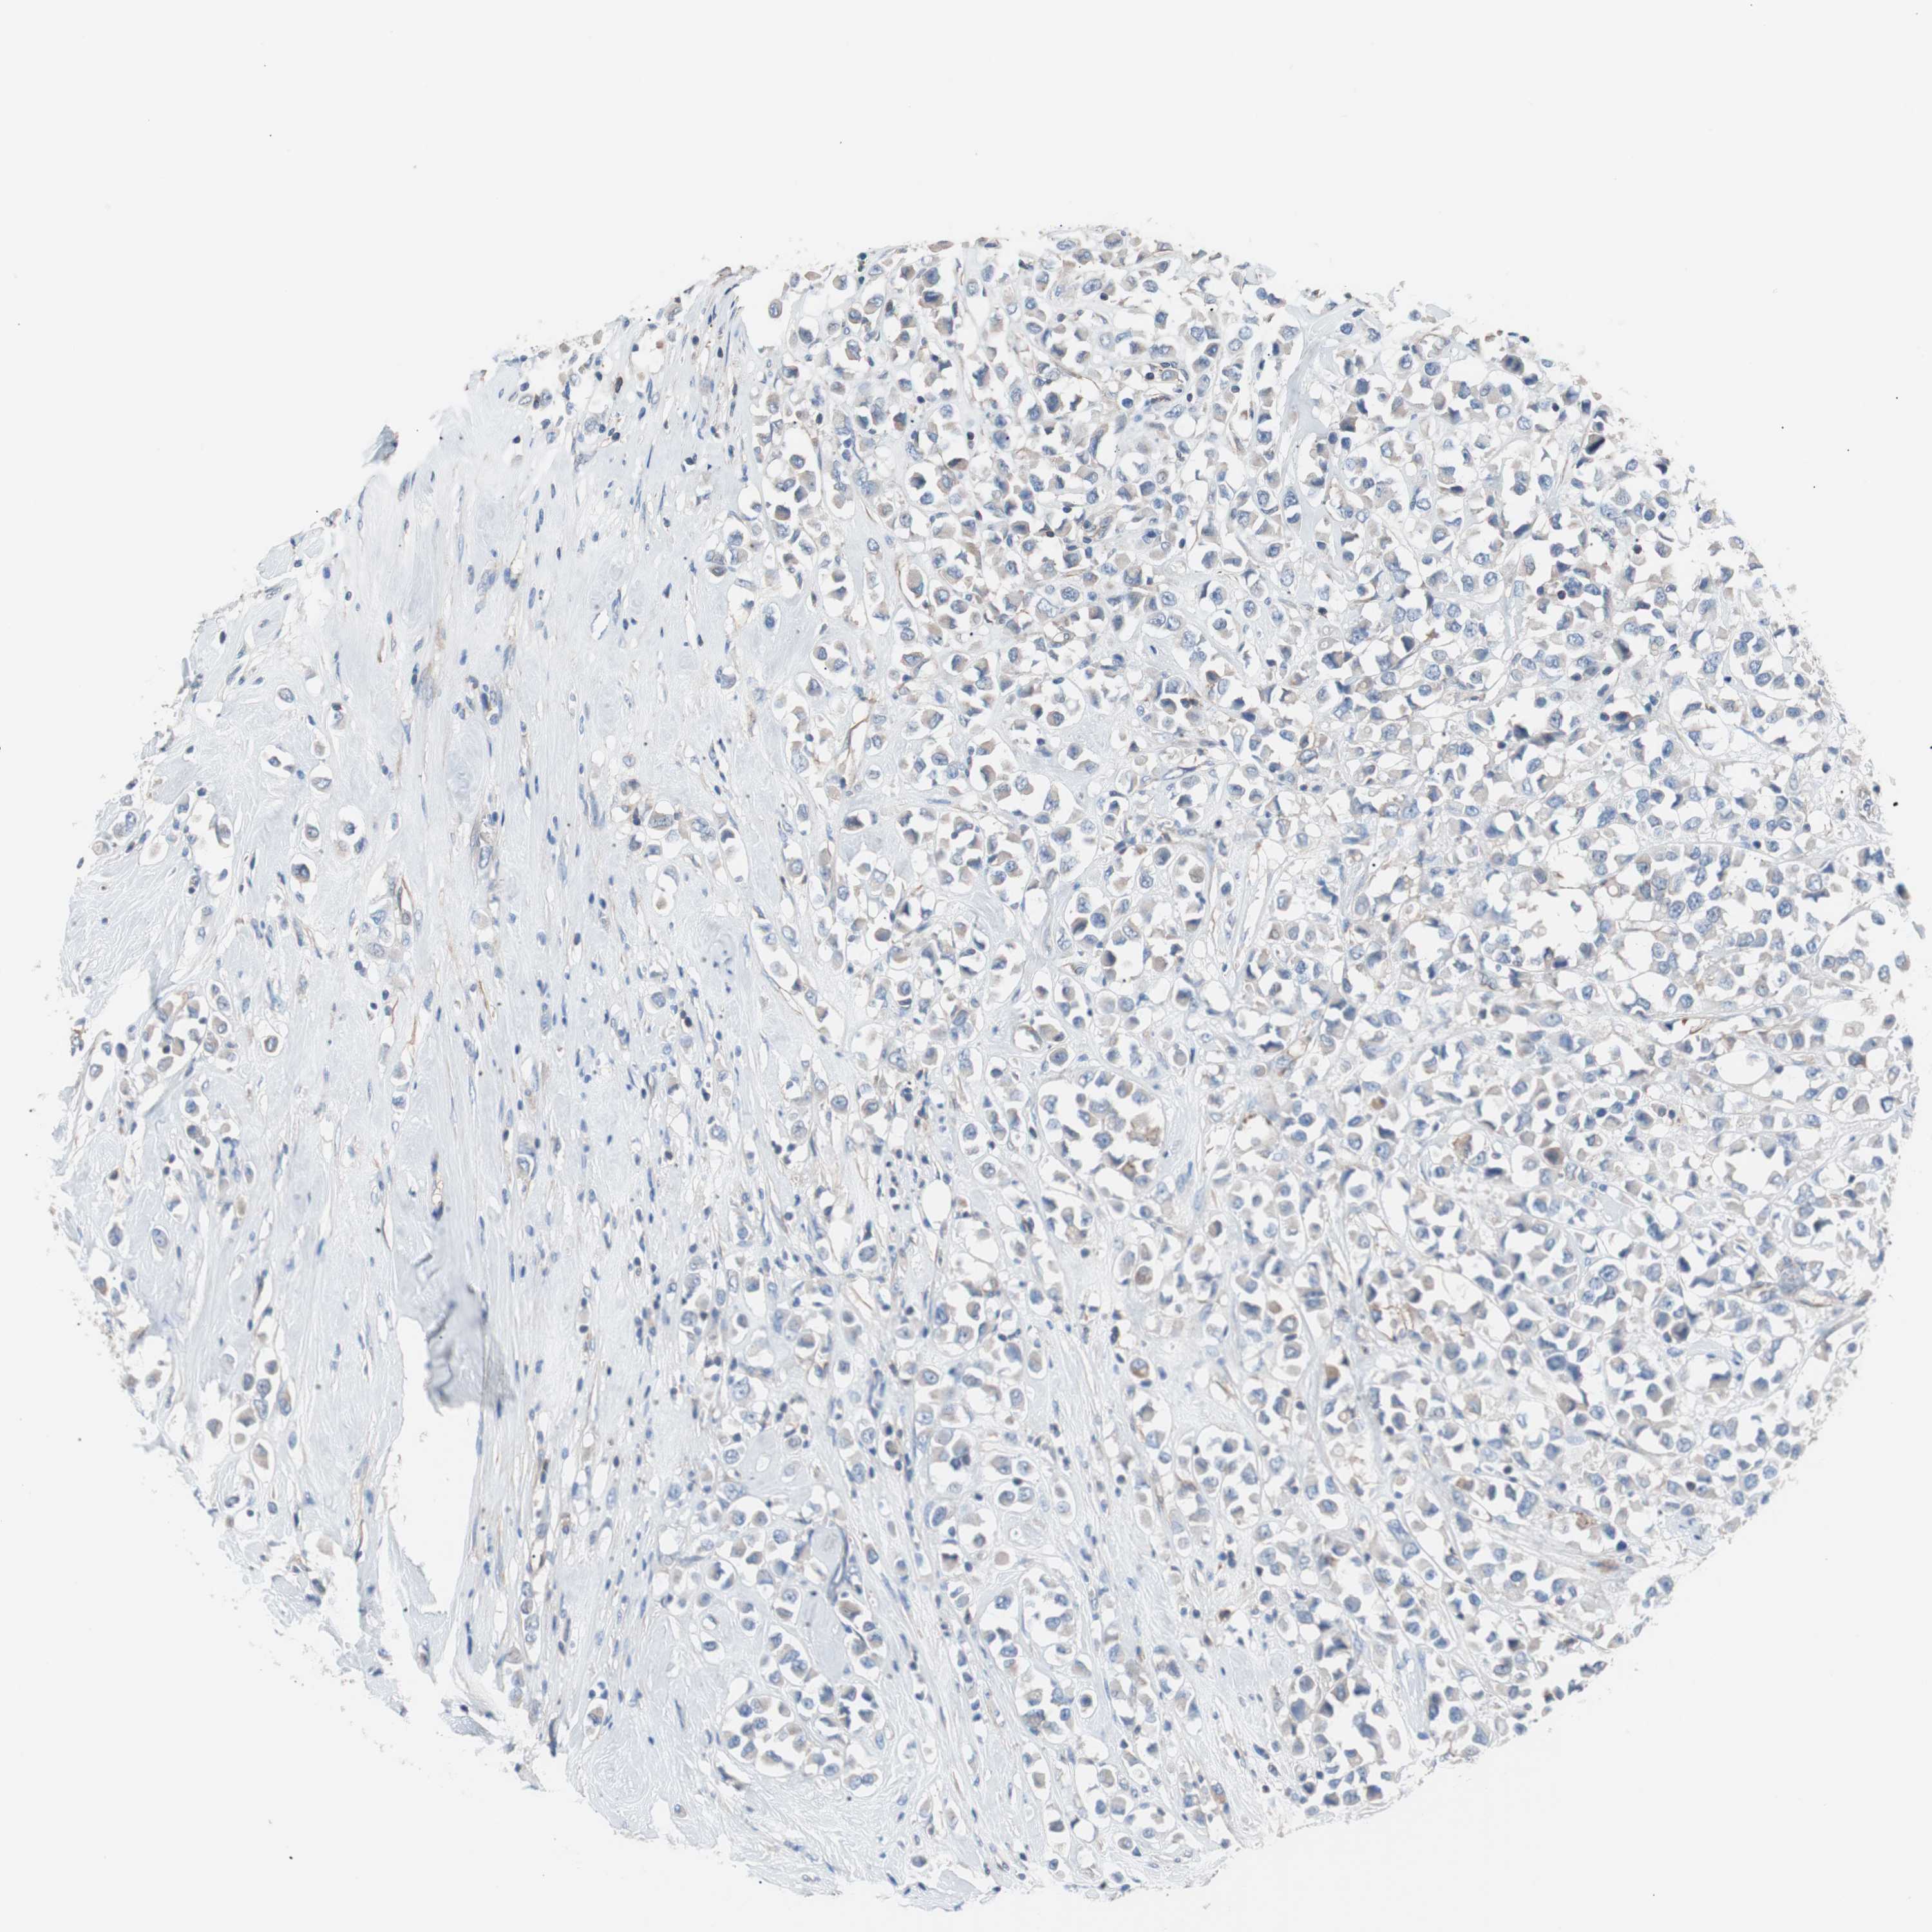

CANCER BREAST CANCER Show tissue menu

BRCA TCGA BRCA VALIDATION PROTEIN EXPRESSION